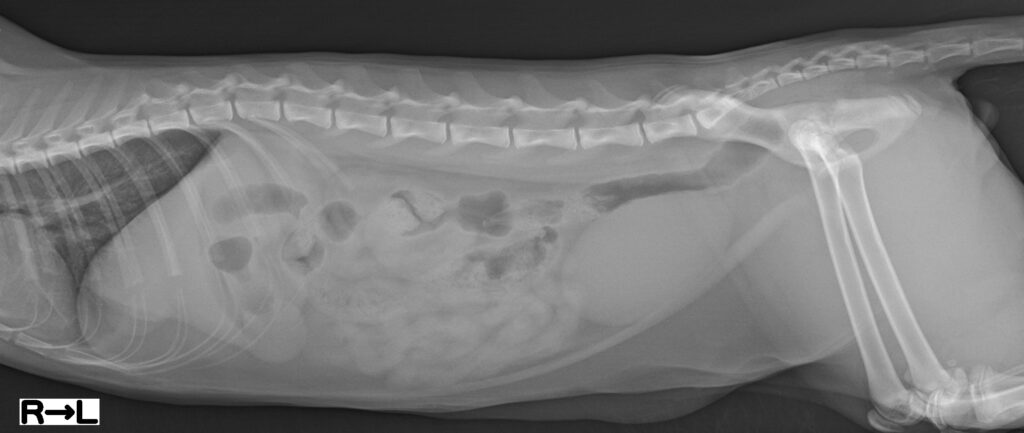

胃幽門部から十二指腸付近に閉塞が疑われる猫の患者として来院しました。来院時は呼吸数42回/分、心拍数180回/分で、反復する嘔吐の既往があり、消化管通過障害が強く疑われる状況でした。腹部レントゲン検査と腹部超音波検査を実施し、画像診断医の評価も踏まえて消化管内異物と判断しました。凝固検査を含む術前検査を行い、全身麻酔下での外科介入が可能かを確認しました。鑑別としては、重度の胃腸炎、腸重積、腫瘤性病変などが挙げられました。

本症例では、開腹下で、消化管を確認し、術前の画像検査通り、消化管に異物を発見しました。腸切開を行い、異物を摘出しました。摘出物はボールの破片と思われ、誤飲と考えられました。